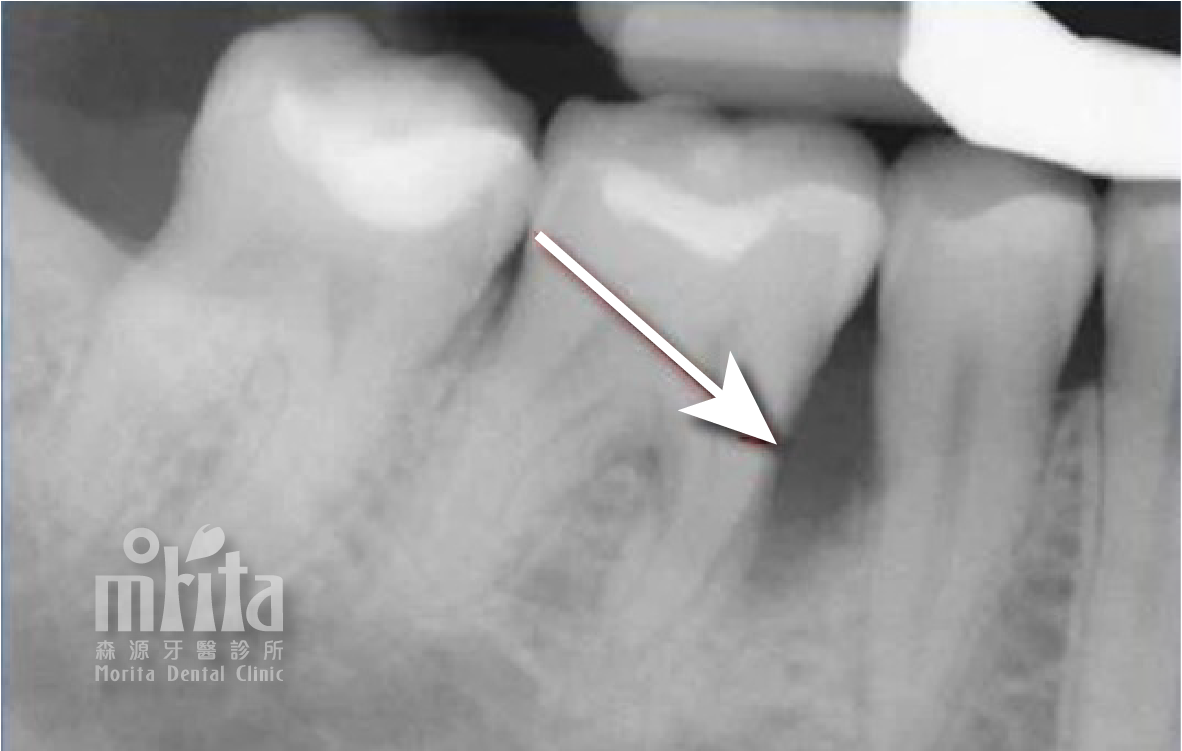

牙冠增長術 Crown Lengthening Procedure

當牙齒因齲齒或是外傷斷裂,造成牙齒的結構脆弱與長度過短時,我們就可以透過牙冠增長術來增加牙齒露出的長度,才能進行齲齒治療,並能增加未來製作假牙的穩定度。

牙冠增長術 術前術後